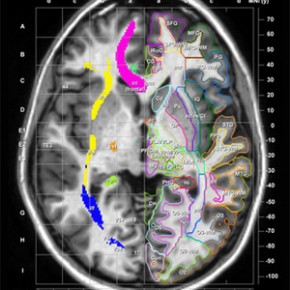

Encontrar y visualizar los tractos de fibra principales de 3 orientaciones y en la RM e Imágenes con tensor de difusión (ITD), y aprender a identificar las principales trayectorias a través del cerebro y su proximidad a las principales estructuras neuroanatómicas.

Desplácese por el cerebro secuencialmente para seguir un tracto de principio a fin. Vea una, dos o las tres orientaciones al mismo tiempo entre las secciones coronal, axial y sagital.

- El formato le permite al observador comparar los cortes coronales, horizontales y sagitales en una sola vista

- Proporciona dos tipos de coordenadas estereotáxicas (coordenadas de Talairach y MNI) para definir las posiciones del cerebro.

- Cincuenta y tres estructuras de materia blanca, 38 áreas corticales, y 22 estructuras profundas de materia gris están definidas y etiquetadas.Además, se define la ubicación de 11 tractos de materia blanca y 36 áreas citoarquitectónicas. Estas estructuras pueden superponerse interactivamente sobre las imágenes dela RM/ITD.

- Las trayectorias de los tractos pueden seguirse de forma secuencial a través del cerebro